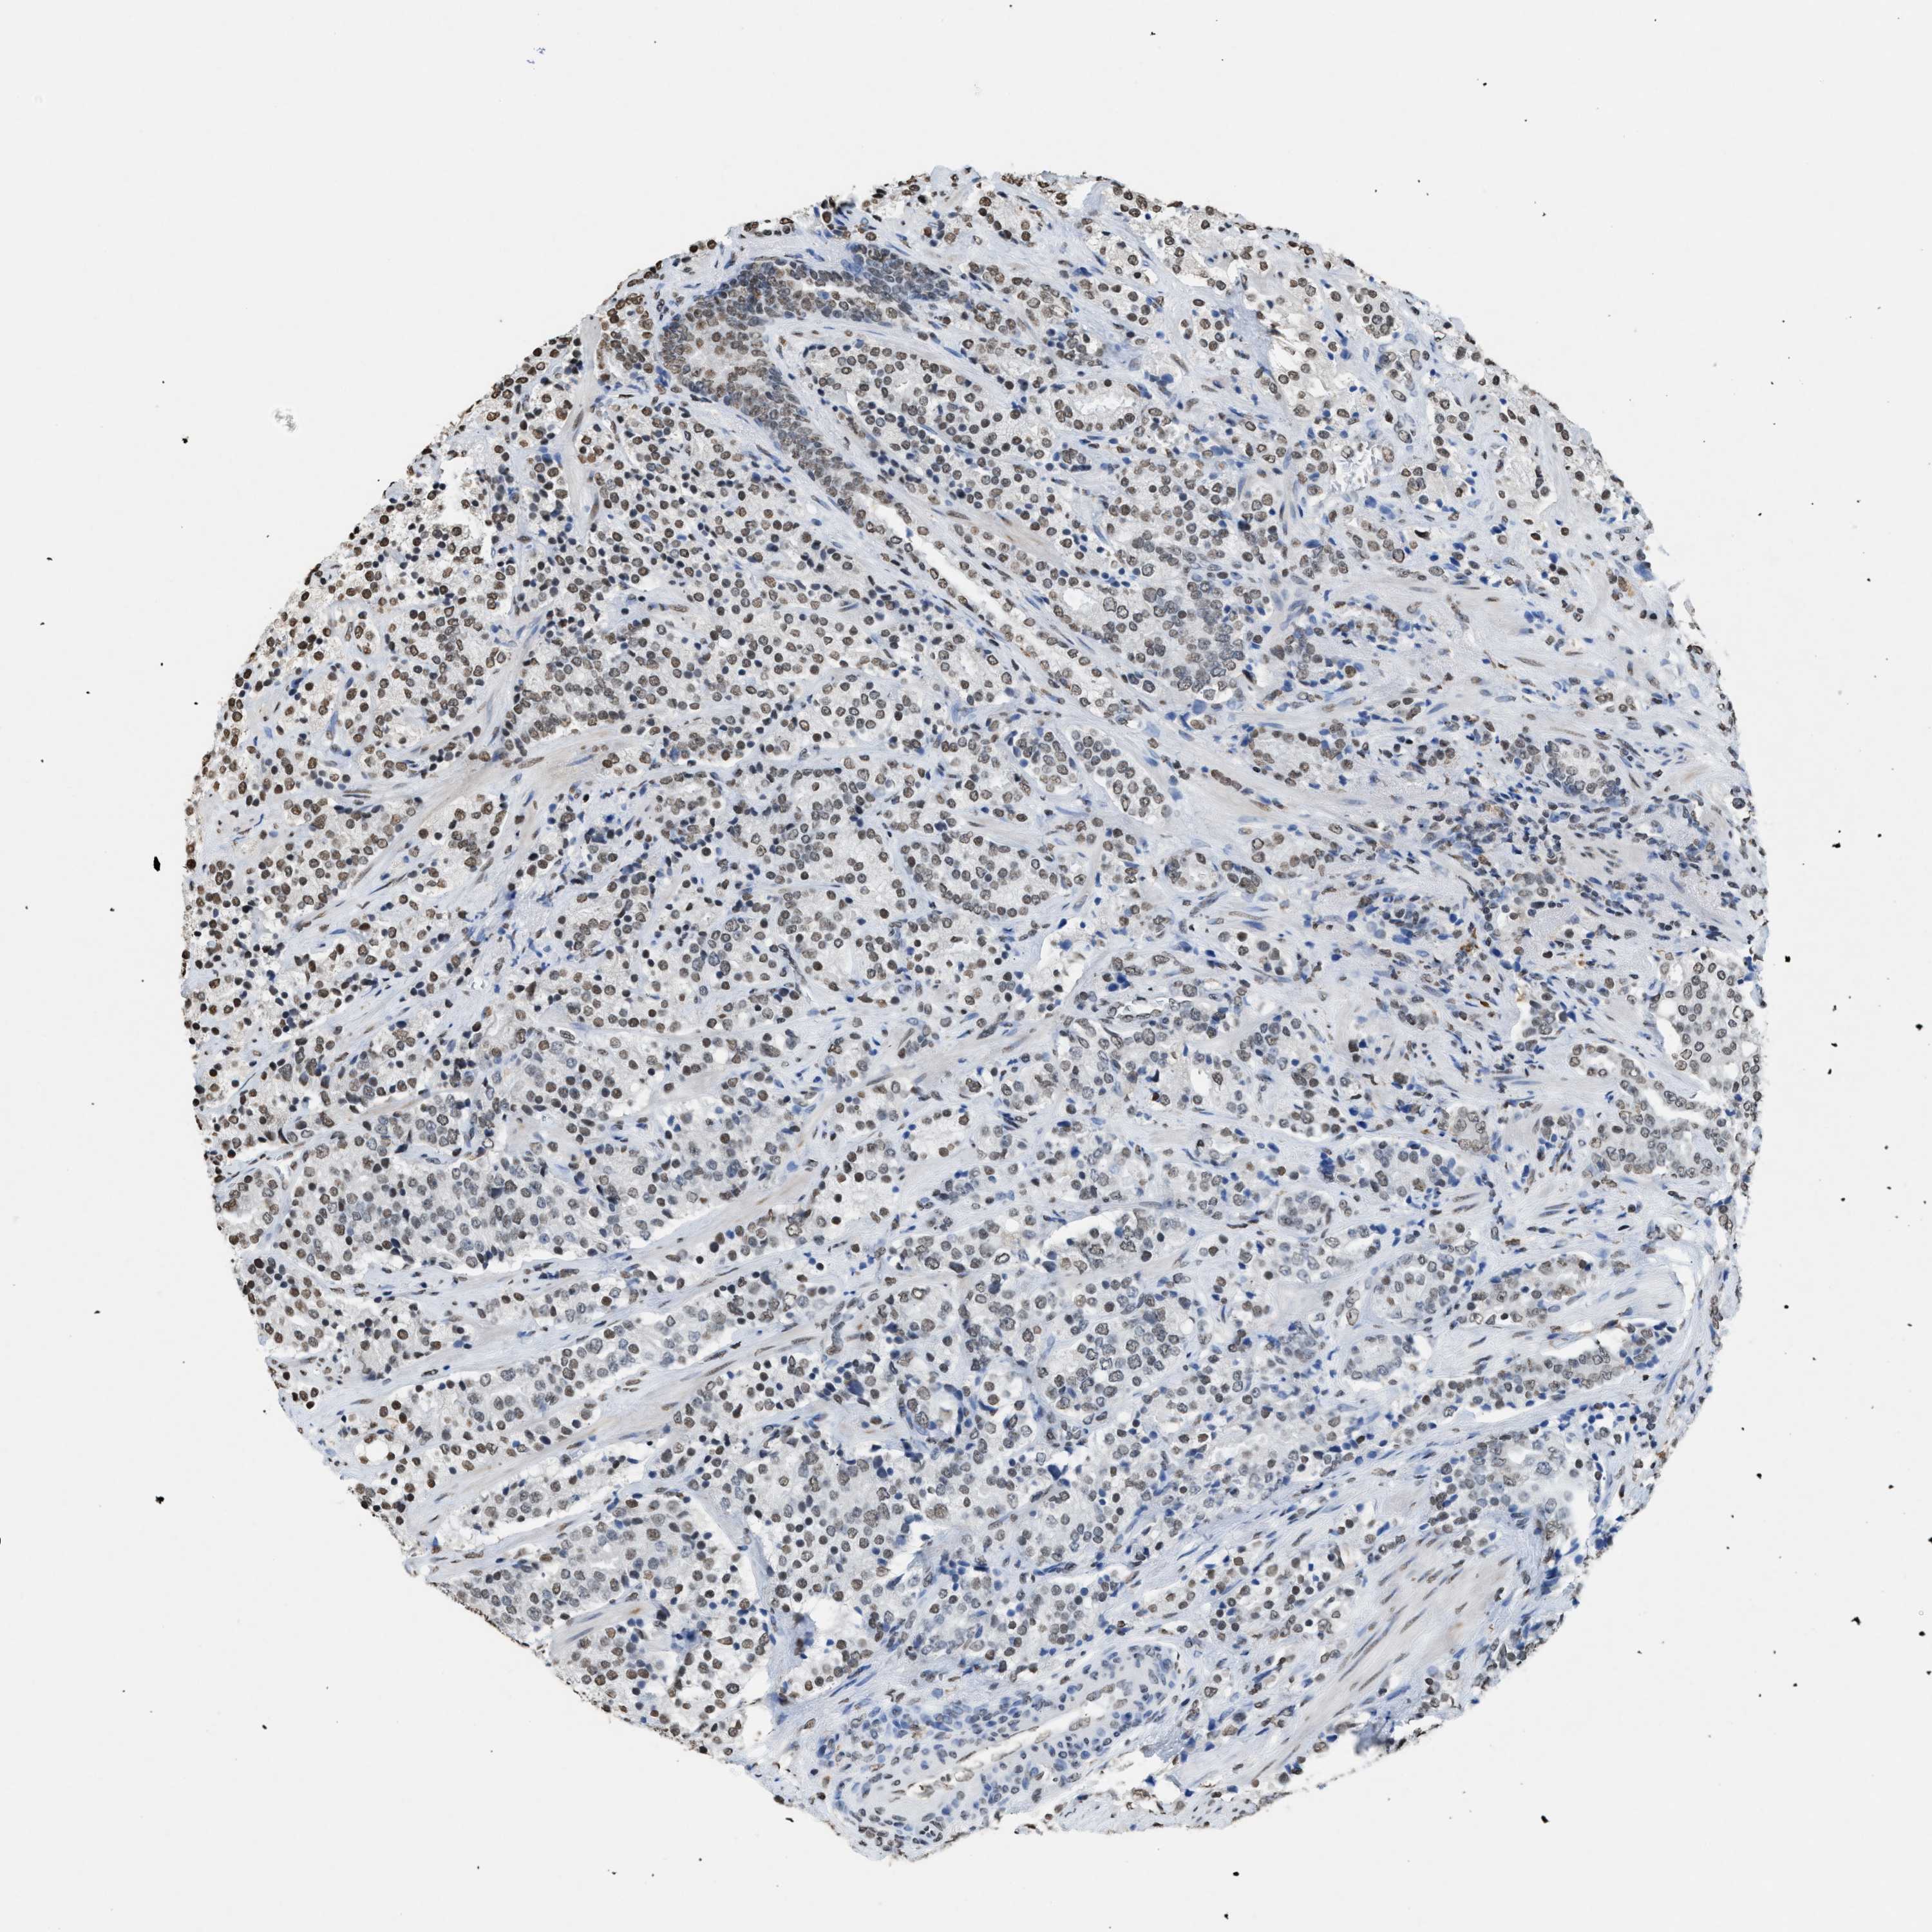

PROSTATE CANCER - Protein expressioni

A mouse-over function shows sample information and annotation data. Click on an image to view it in a full screen mode. Samples can be filtered based on level of antibody staining by selecting one or several of the following categories: high, medium, low and not detected. The assay and annotation is described here.

Antibody stainingi

Antibody staining in the annotated cell types in the current human tissue is reported as not detected, low, medium, or high, based on conventional immunohistochemistry profiling in selected tissues. This score is based on the combination of the staining intensity and fraction of stained cells.

Each image is clickable and will lead to virtual microscopy that enables deeper exploration of all samples and also displays staining intensity scores, fraction scores and subcellular localization as well as patient and tissue information for each sample.

Antibody HPA021816

Antibody CAB002209

Staining

High

Medium

Low

Not detected

Intensity

Strong

Moderate

Weak

Negative

Quantity

>75%

75%-25%

<25%

None

Location

Nuclear

Cytoplasmic/membranous

Cytoplasmic/membranous,nuclear

Adenocarcinoma, High grade

Adenocarcinoma, Low grade

Adenocarcinoma, Medium grade